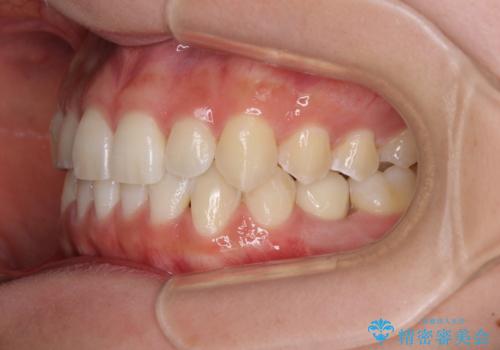

- 前歯の叢生と、奥歯の咬み合わせの悪さを気にして来院された患者様です。

左下には後続永久歯の欠損した乳歯が残存しており、叢生を相まって咬合関係が乱れていました。

乳歯は抜歯し、インビザラインにて矯正治療を行いながら、並行してインプラントによる補綴治療を行うこととしました。